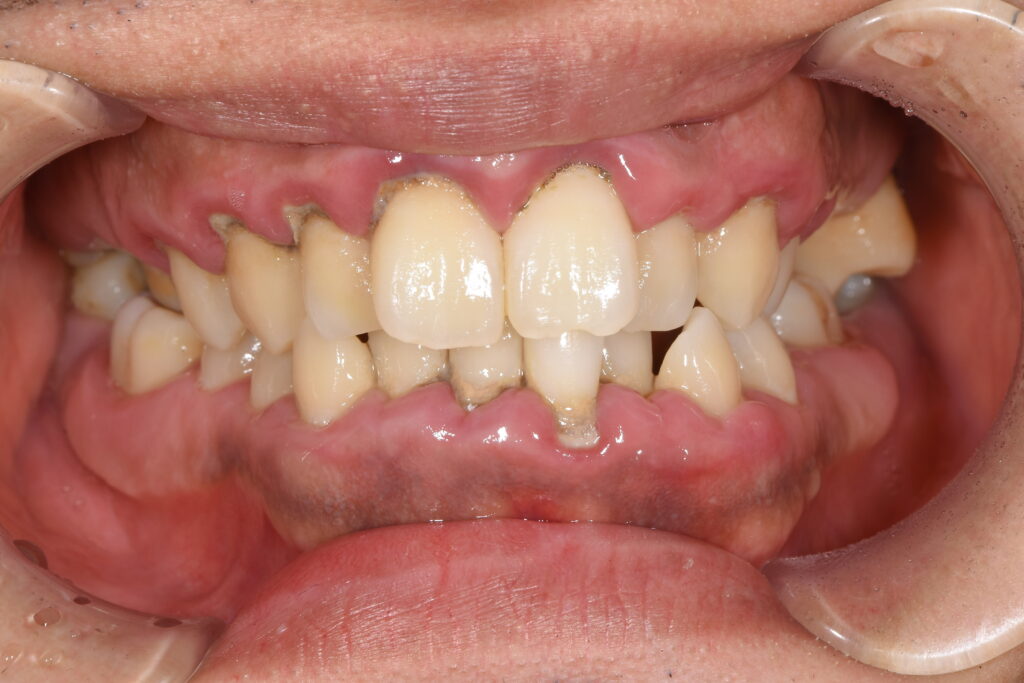

まずは初診時の状態です。

【初診時】

初診時、歯周病・虫歯も進行しており、まずは初期治療として歯周病治療・虫歯治療を行いました。

③歯並びに関して、問題点は歯列弓の狭窄を認め、歯がガタガタになってしまっています。また、上顎の歯が突出してしまい、出っ歯になっています。